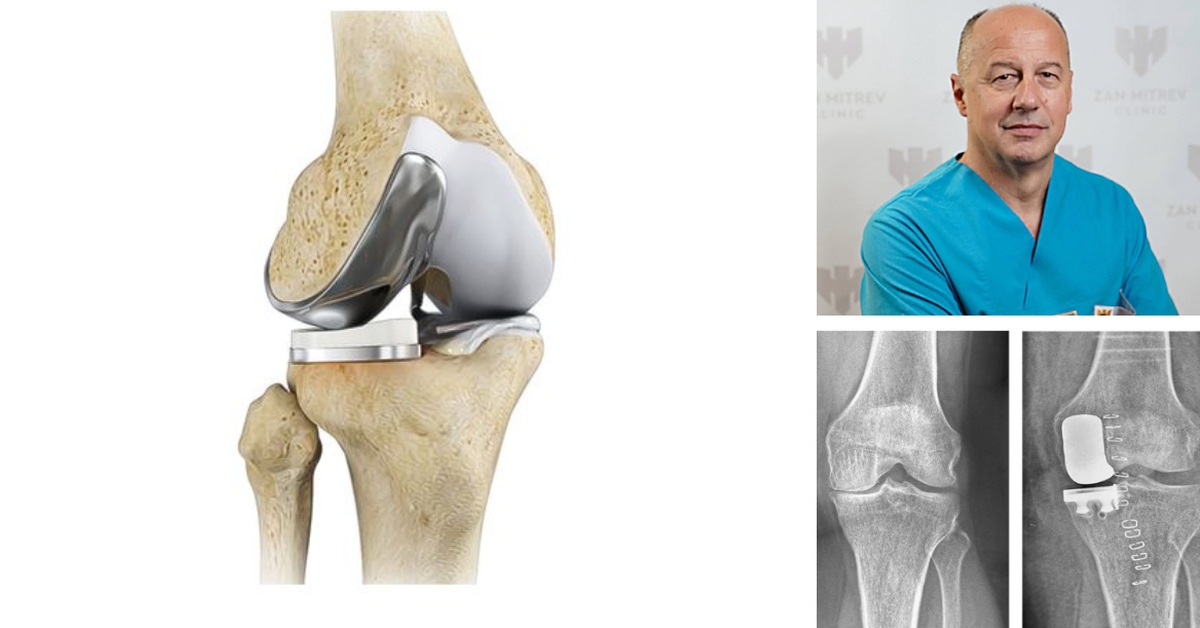

Уникондиларна ендопротеза на колено е минимално инвазивна процедура во однос на тоталната ендопротеза, при која што само оштетениот дел на коленото се заменува со имплант. Се нарекува уште и парцијална, односно делумна ендопротеза на колено.

Коленовиот зглоб е поделен на 3 компартмани (делови): медијален (внатрешен), латерален (надворешен) и пателофеморален компартман.

Уникондиларната ендопротеза е хируршка опција кај пациенти кај кои што дегенеративните промени зафаќаат само еден дел од коленото (најчесто внатрешниот), додека останатите зглобни површини се интактни-незасегнати, однoсно не се оштетени.

Со мал рез се пристапува до оштетениот дел на коленото. Се отстранува оштетениот дел од менискусот, минимално се ресецира оштетениот дел на коската на тибијата и фемурот и се поставува имплант во коленото. Не се поставува постоперативна дренажа.